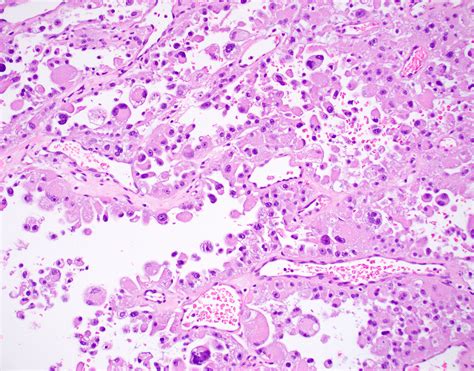

ASPS is a type of soft tissue sarcoma that originates from the mesenchymal cells, which are responsible for the formation of connective tissues. The disease is named for its distinctive alveolar pattern under the microscope, which resembles the structure of lung alveoli. This pattern is a key diagnostic feature that helps differentiate ASPS from other types of sarcomas.

Histopathological examination reveals the characteristic alveolar pattern of ASPS, which is essential for a definitive diagnosis. Additionally, immunohistochemical staining and molecular genetic testing can provide further confirmation.